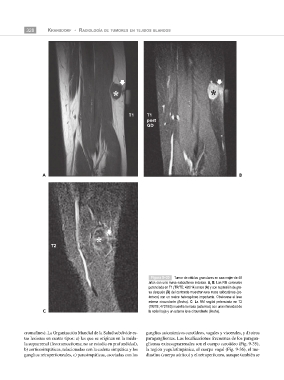

Figura 9–30 Tumor de células granulares en una mujer de 48

años con una masa subcutánea indolora. A, B: Las RM coronales

potenciada en T1 (TR/TE; 420/14) antes (A) y con supresión de gra-

sa después (B) del contraste muestran una masa subcutánea (as-

terisco) con un realce heterogéneo importante. Obsérvese el leve

edema circundante (flecha). C: La RM sagital potenciada en T2

(TR/TE; 4737/60) muestra la masa (asterisco) con una intensidad de

C la señal baja y un edema leve circundante (flecha).